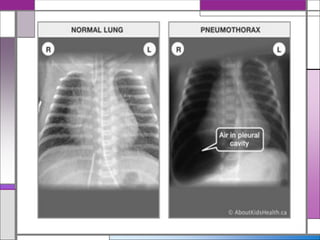

Chest X-ray : There are no diagnostic features of

asthma on the chest X-ray

A chest X-ray may be helpful in excluding a

pneumothorax, which can occur as a complication

of asthma